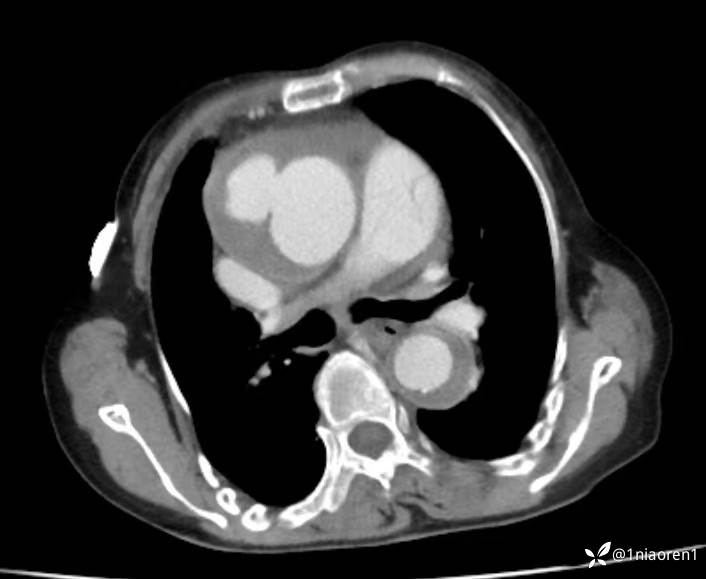

病例又碰到了一个夹层饼干

考虑什么诊断,哪一型?